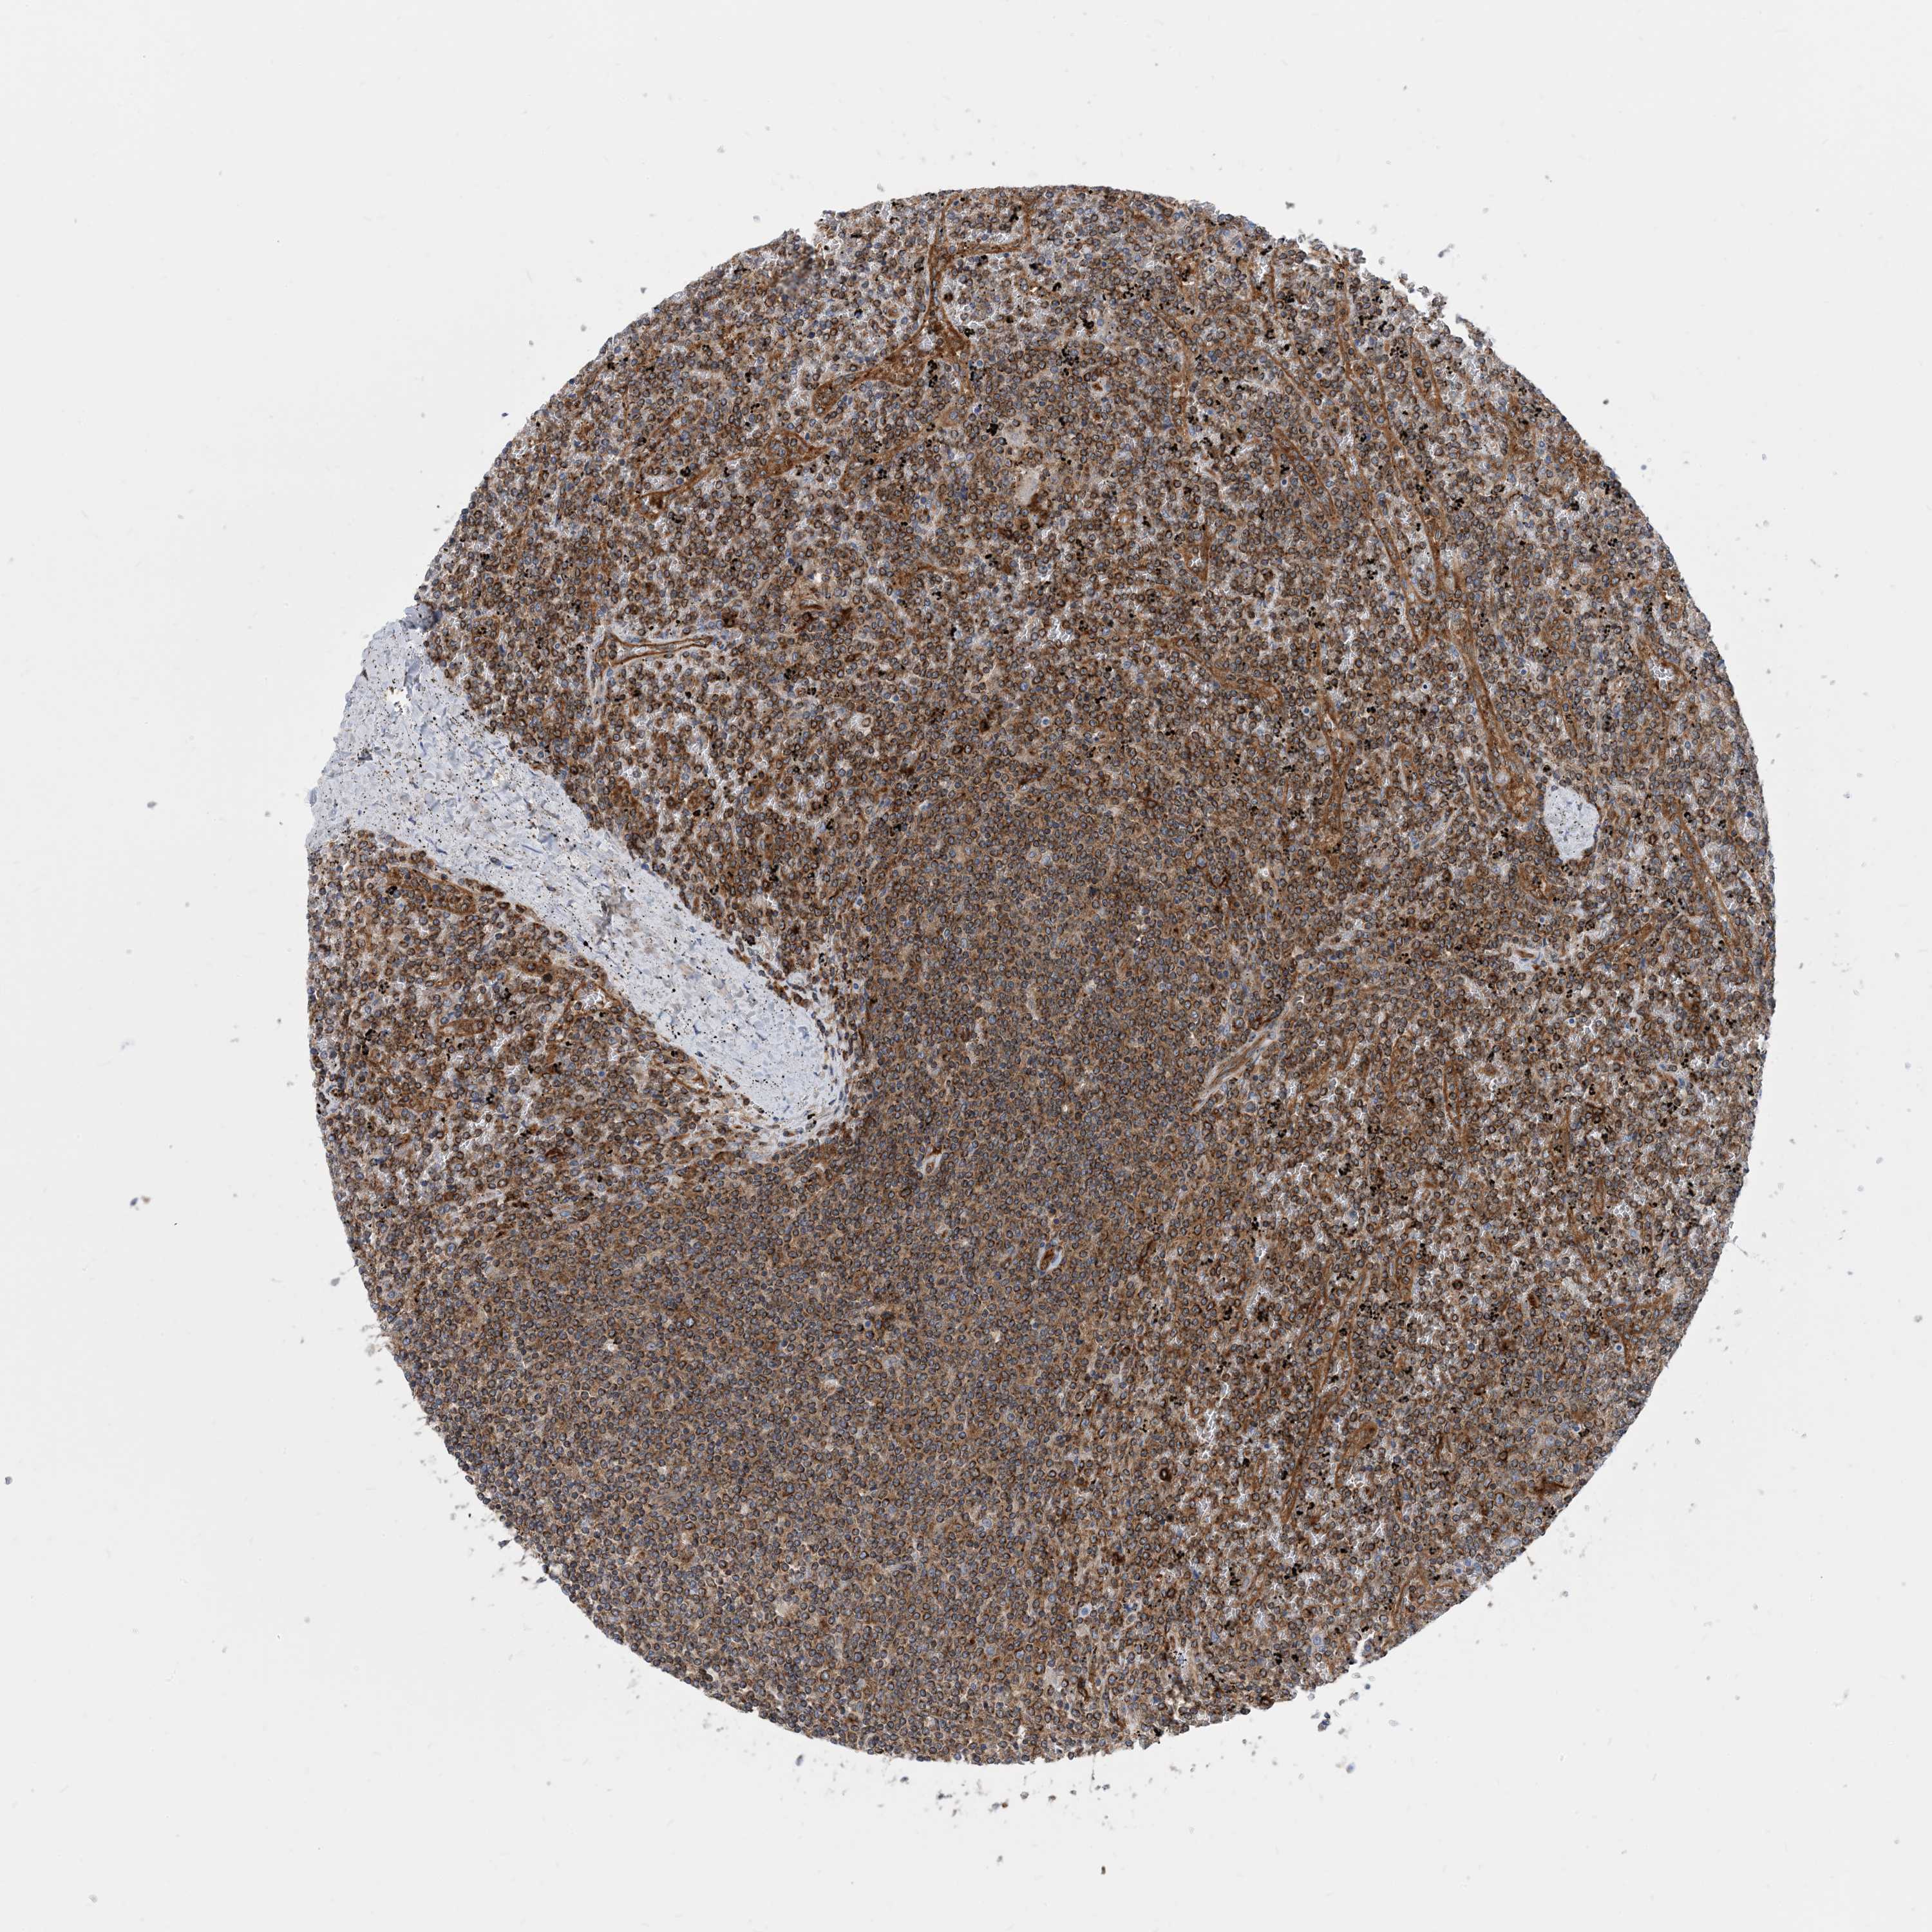

CANCER LYMPHOMA Show tissue menu

LYMPHOMA - Protein expressioni

A mouse-over function shows sample information and annotation data. Click on an image to view it in a full screen mode. Samples can be filtered based on level of antibody staining by selecting one or several of the following categories: high, medium, low and not detected. The assay and annotation is described here.

Each image is clickable and will lead to virtual microscopy that enables deeper exploration of all samples and also displays staining intensity scores, fraction scores and subcellular localization as well as patient and tissue information for each sample.

Antibody HPA035013

Staining

High

Medium

Low

Not detected

Intensity

Strong

Moderate

Weak

Negative

Quantity

>75%

75%-25%

<25%

None

Location

Nuclear

Cytoplasmic/membranous

Cytoplasmic/membranous,nuclear

Hodgkin's disease, NOS

Malignant lymphoma, non-Hodgkin's type, High grade

Malignant lymphoma, non-Hodgkin's type, Low grade